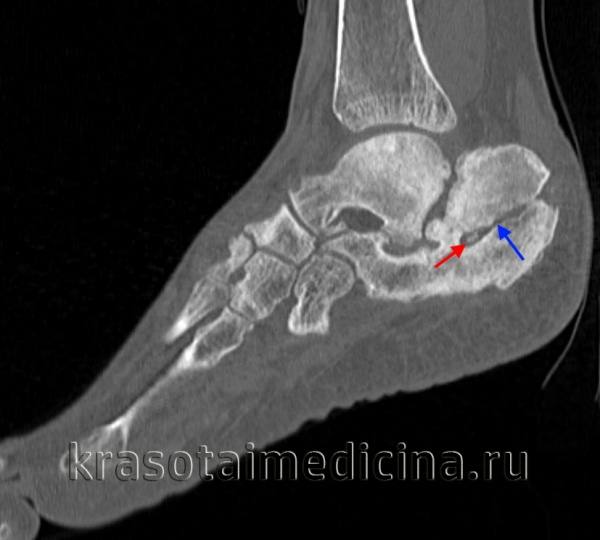

МРТ стопы. Остеомиелит таранной и большеберцовой кости с наличием обширной зоны деструкции костной ткани.

КТ стопы. Посттравматический хронический остеомиелит пяточной кости с наличием секвестра (красная стрелка) и свищевого хода (синяя стрелка).